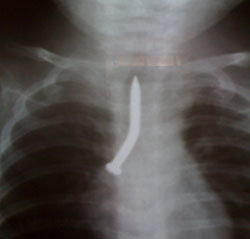

Bé M.H.N.T., 6 tháng tuổi, sống ở Nha Trang, Khánh Hòa. Cách đó 20 ngày bé chơi với người chị, người nhà phát hiện người chị đưa tay vào trong miệng bé để lấy vật gì không rõ, bé tím tái, ho sặc sụa, trong miệng có ít máu chảy ra. Sau đó bé hay ho, sốt, người nhà đưa bé đi khám bệnh uống thuốc nhiều nơi nhưng tình trạng bệnh ngày càng nặng hơn. Khi bé đến khám ở bệnh viện tỉnh, được chụp X-quang thì phát hiện cây đinh trong phổi. Bé được chuyển đến Bệnh viện Nhi Đồng 1 trong tình trạng khó thở.

Tại khoa tai mũi họng Bệnh viện Nhi Đồng 1, bé được soi cấp cứu và đã gắp ra một cây đinh dài 3,5cm nằm lọt vào phế quản góc bên phải. Sau bảy ngày điều trị bé đã được xuất viện.